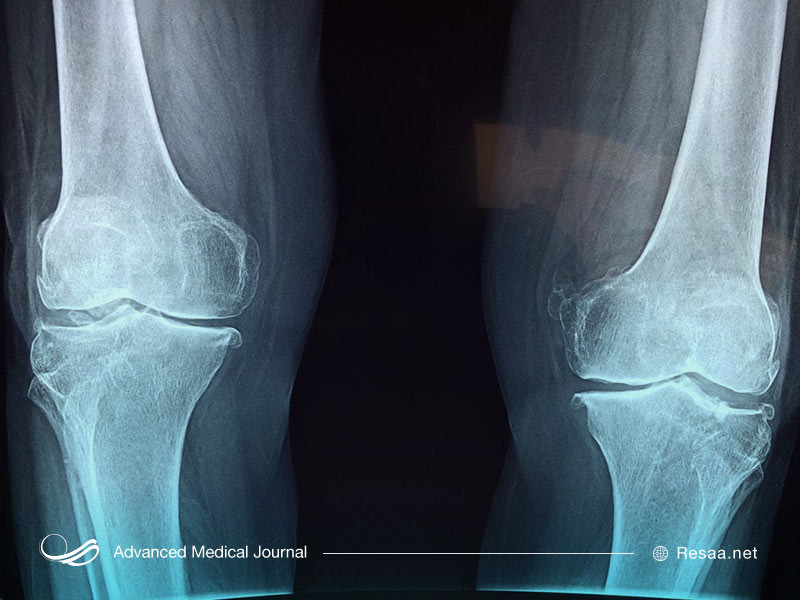

به طور معمول تصویربرداری مانند اشعه ایکس برای بررسی شکستگی و تغییرات استخوان پیشنهاد میشود. اسکن تراکم استخوان (DEXA) میتواند در کودکان با وزن بیش از 10 کیلوگرم انجام شود اما اطلاعات کافی برای ارائه نتایج دقیق در کودکان زیر پنج سال در دسترس نیست. آزمایش ژنتیک امکانپذیر است اما به طور معمول انجام نمیگردد. همچنان OI یک تشخیص بالینی است.

پزشک میتواند با استفاده از اشعه ایکس بیماری شکنندگی استخوان را تشخیص دهد. اشعه ایکس به پزشک اجازه میدهد استخوانهای شکسته فعلی و قدیمی را ببیند. همچنین این روش، مشاهده نقص در استخوانها را برای آنها آسان میکند. از آزمون آزمایشگاهی ممکن است به منظور تجزیه و تحلیل ساختار کلاژن کودک شما استفاده شود. در برخی موارد ممکن است پزشک شما بخواهد بیوپسی با پانچ پوست “skin punch biopsy” انجام دهد. در طی این نمونه برداری، پزشک از یک لوله توخالی و تیز استفاده میکند تا نمونه کوچکی از بافت شما را بردارد.

- تغییر شکل استخوان

- چندین استخوان شکسته

- استخوان ها ممکن است شکلی تغییر یافته داشته باشند به عنوان مثال این امکان وجود دارد که کوتاه یا خمیده شوند.